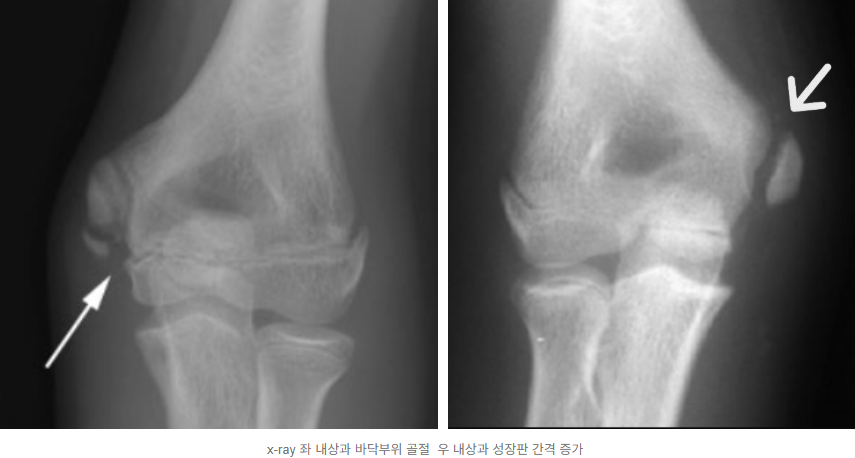

영상 촬영(X-ray, 초음파, MRI): X-ray로 뼈의 석회화, 성장판 손상 등을 확인하고, 초음파로 힘줄과 인대 손상 여부를 빠르게 파악할 수 있습니다. 필요한 경우 MRI로 미세 손상이나 조직 변화를 정밀하게 진단합니다.